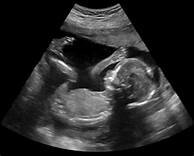

• 3rd Trimester

3rd Trimester

Months 7 through 9, the last trimester. At the start of this trimester the fetus is about 10-12 inches in length and weighs around 2-3 pounds. Throughout this trimester the fetus will grow an additional 3-4 inches and gain about 6-8 pounds. The organs increase their activity and the development of limbs, nerves, and muscles will strengthen its ability to move on its own.